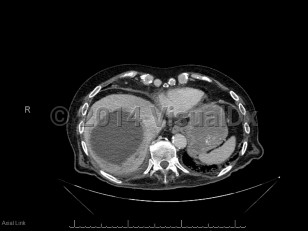

Pyogenic liver abscess

A pyogenic liver abscess is a collection of pus in the liver as the result of bacterial (or rarely fungal) infection.